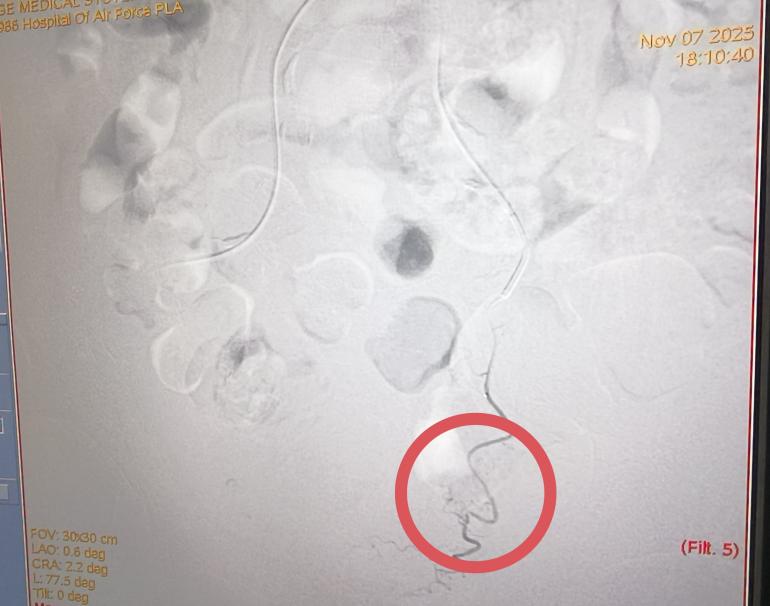

术前 术后

11月7日下午,手术正式进行,全程在患者清醒状态下完成,痛苦小,术后仅需对穿刺点进行加压包扎,恢复迅速。术后第二天,李老先生即可下床活动,身体恢复良好,目前已康复出院。